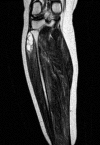

Peripheral neuropathies caused by ganglion cysts are rare. They seldom cause serious complications especially in the lower extremities. The case was a 51-year-old woman referred by her physician to the vascular surgeon with diagnosis including intermittent (vascular) claudication and deep venous thrombosis. Primarily vascular surgeon performed a doppler ultrasound of the lower extremity and calculation of the ankle-brachial index. There were no abnormal pathological findings. Careful physical examination revealed soft swelling and tenderness around the fibular head and neck. Weakness was observed in foot eversion and dorsiflexion. There was pain and tingling in the distribution of the peroneal nerve. and referring the patient to orthopedic surgeon owing to concern for a potential compressive lesion at the right proximal tibiofibular region. Electromyogram studies and physical examination confirmed a diagnosis of compression neuropathy of common peroneal nerve. Magnetic resonance imaging revealed a fluid-filled, lobulated mass indicating a ganglion cyst. One months after decompression, the patient had no complaint. Fast diagnosis and immediate management are essential to regain best possible recovery.